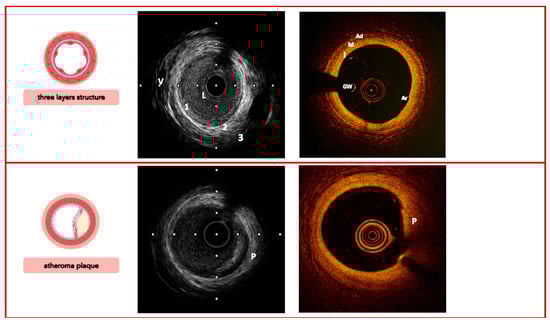

4. Characterization of Plaque Morphology

- Yabushita, H.; Bouma, B.E.; Houser, S.L.; Aretz, H.T.; Jang, I.K.; Schlendorf, K.H.; Kauffman, C.R.; Shishkov, M.; Kang, D.H.; Halpern, E.F.; et al. Characterization of human atherosclerosis by optical coherence tomography. Circulation 2002, 106, 1640–1645. [Google Scholar] [CrossRef] [PubMed]

- Ziad, A.; Galougahi, K.K.; Gary, S.M.; Maehara, A.; Richard, S.; Shlofmitz, R.; Mattesini, A. Intracoronary optical coherence tomography: State of the art and future directions. EuroIntervention 2021, 17, e105–e123. [Google Scholar] [CrossRef]